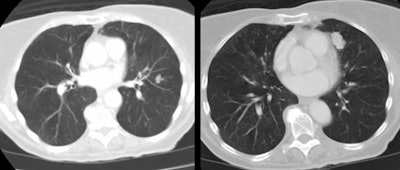

| Multiple carcinoids and tumorlets: The

patient shown below had a history of breast cancer and

presented with multiple, slowly enlarging lung nodules. A

dominant nodules was seen in the lingula, with multiple

other, scattered nodules that measured less than 1 cm. On

resection, the patient was found to have multiple pulmonary

carcinoids and tumorlets. |